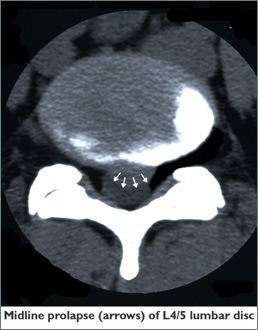

The operation is commonly offered to patients for relief of leg pain referred from lumbar spine due to herniated disc(s) exerting pressure on roots of the sciatic nerve. It is also offered for other manifestations of pressure on lumbar nerve roots, including weakness (for example an inability to lift the foot at the ankle, termed “foot-drop”) or disturbance in sensation.

Once your pinched nerve is located, the extent of the pressure on the nerve can be determined. Using microsurgical techniques, your surgeon removes the herniated portion of the disc as well as any disc fragments that have broken off from the disc. It is also important that the surgeon flushes out the loose stringy material inside the disc, to prevent more of this material coming out (called a “re-prolapse”) in the early post-operative period.